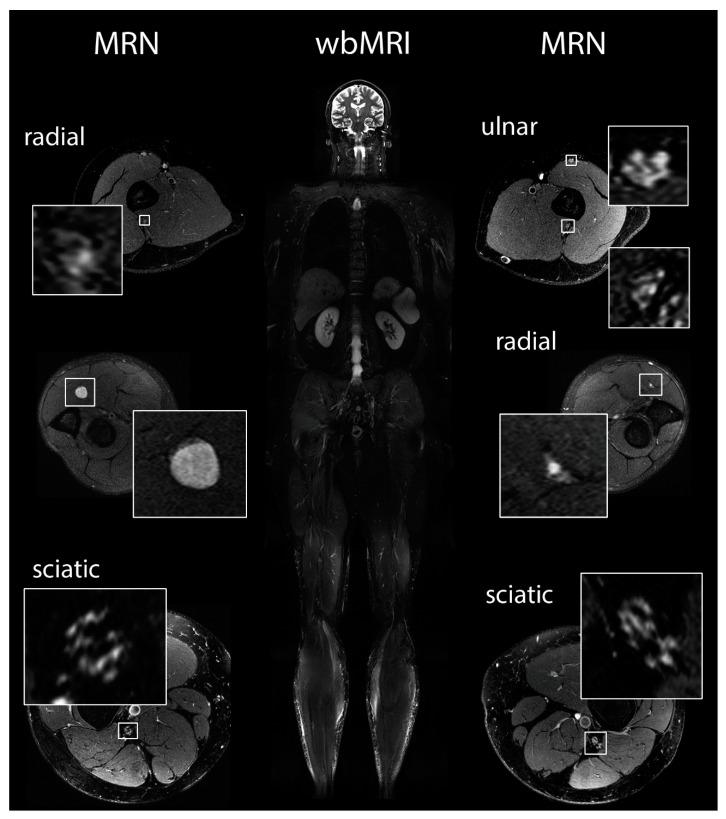

Schwannomatosis is the third form of neurofibromatosis and characterized by the occurrence of multiple schwannomas. The most prominent symptom is chronic pain. We aimed to test whether pain in schwannomatosis might be caused by small-fiber neuropathy. Twenty patients with schwannomatosis underwent neurological examination and nerve conduction studies. Levels of pain perception as well as anxiety and depression were assessed by established questionnaires. Quantitative sensory testing (QST) and laser-evoked potentials (LEP) were performed on patients and controls. Whole-body magnetic resonance imaging (wbMRI) and magnetic resonance neurography (MRN) were performed to quantify tumors and fascicular nerve lesions; skin biopsies were performed to determine intra-epidermal nerve fiber density (IENFD). All patients suffered from chronic pain without further neurological deficits. The questionnaires indicated neuropathic symptoms with significant impact on quality of life. Peripheral nerve tumors were detected in all patients by wbMRI. MRN showed additional multiple fascicular nerve lesions in 16/18 patients. LEP showed significant faster latencies compared to normal controls. Finally, IENFD was significantly reduced in 13/14 patients. Our study therefore indicates the presence of small-fiber neuropathy, predominantly of unmyelinated C-fibers. Fascicular nerve lesions are characteristic disease features that are associated with faster LEP latencies and decreased IENFD. Together these methods may facilitate differential diagnosis of schwannomatosis.

神经鞘瘤病是神经纤维瘤病的第三种形式,其特征是多发性神经鞘瘤的发生。最突出的症状是慢性疼痛。我们旨在测试神经鞘瘤病患者的疼痛是否可能是由小纤维神经病引起的。20 名神经鞘瘤病患者接受了神经系统检查和神经传导研究。通过既定的问卷评估疼痛感知水平以及焦虑和抑郁程度。对患者和对照组进行定量感觉测试(QST)和激光诱发电位(LEP)。进行全身磁共振成像(wbMRI)和磁共振神经成像(MRN)以量化肿瘤和束状神经病变;进行皮肤活检以确定表皮内神经纤维密度(IENFD)。所有患者均患有慢性疼痛,无进一步的神经功能缺损。问卷表明存在有明显生活质量影响的神经病理性症状。wbMRI 在所有患者中均检测到周围神经肿瘤。MRN 在 16/18 名患者中显示出额外的多发性束状神经病变。LEP 与正常对照组相比潜伏期明显更快。最后,13/14 名患者的 IENFD 明显降低。因此,我们的研究表明存在小纤维神经病,主要是无髓鞘 C 纤维。束状神经病变是特征性疾病特征,与更快的 LEP 潜伏期和降低的 IENFD 相关。这些方法可以共同促进神经鞘瘤病的鉴别诊断。